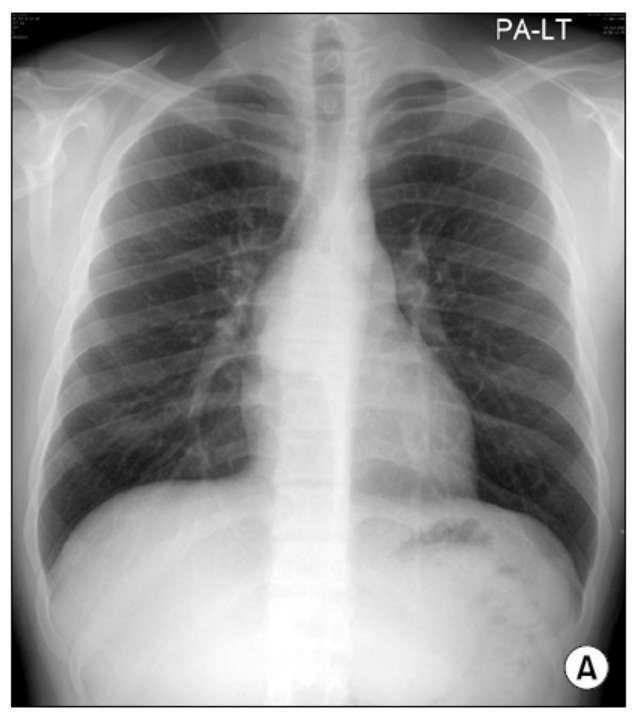

20¼¼ ³²ÀÚ, ½Åü °ËÁø X-ray »ó ¿ì¿¬È÷ ¹ß°ßµÈ ÀÌ»ó ¼Ò°ß ÁÖ¼Ò·Î ³»¿øÇÏ¿´½À´Ï´Ù.

Ưº°È÷ È£¼ÒÇÏ´Â Áõ»óÀº ¾ø¾ú°í lab »ó ÀÌ»ó ¼Ò°ßÀº º¸ÀÌÁö ¾Ê¾Ò½À´Ï´Ù.